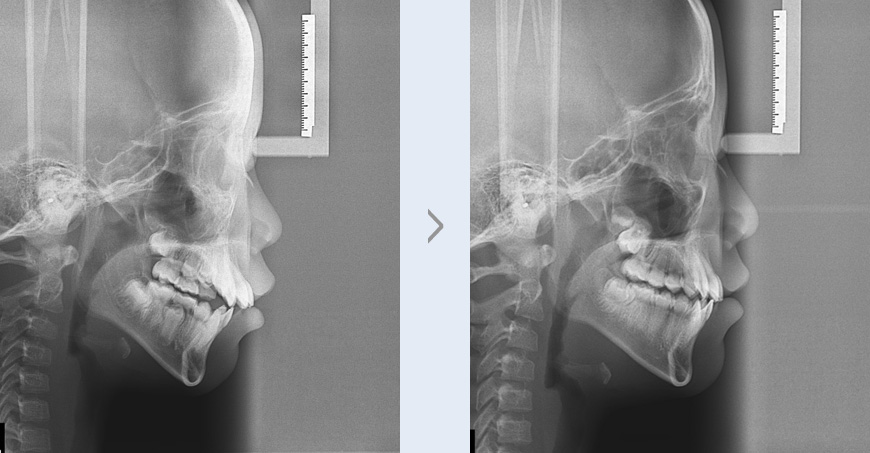

앞니가 나와 보이고 점점 틀어지며 입을 벌리고 자는 증상으로 내원한 초등학교 4학년 여학생입니다.

진단 결과 아래턱의 발육이 부족하고 턱뼈의 폭이 좁아져 발생한 돌출입(골격성 2급 부정교합) 증상을

확인하였습니다. 정상적인 골격 성장을 유도하기 위해 상대적으로 돌출된 위턱에는 성장을 억제할 수 있는

헤드기어를, 상대적으로 발육이 더딘 아래턱은 성장 촉진을 위해 액티베이터를 착용하였습니다.

돌출되어 있던 앞니가 정상적인 위치로 이동하였으며, 발육이 다소 더디던 아래턱이 균형 있게

성장하였습니다. 틀어져 있던 치아도 더 가지런해졌고 입을 벌리고 자던 증상 또한 개선 되어 심미적인

부분과 기능적인 부분 모두 만족을 얻으셨습니다.